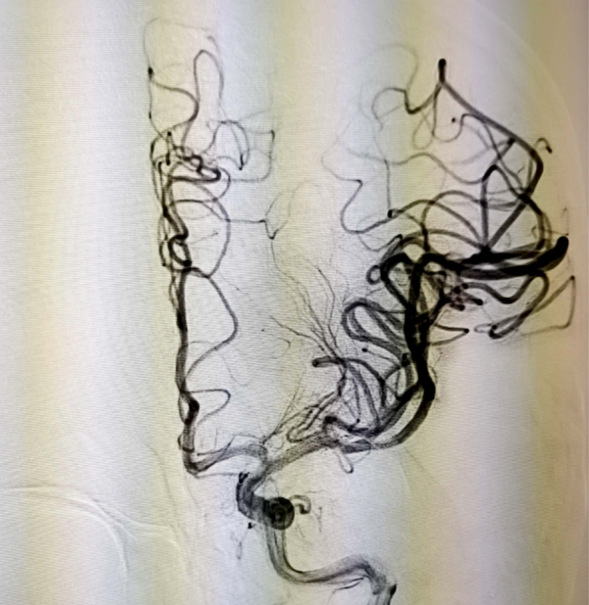

术后颈内动脉正位造影

术后颈内动脉侧位造影

当天15点47分,一位老年男性患者在家中看电视时突发右侧肢体活动不灵,不能言语,家属紧急将其送往我院急诊就诊并联系神经内五科迟景宏主任。16点40分,患者在家属陪同下来到我院急诊。迟景宏主任在紧急查看患者病情并完善相关检查后,果断判断患者为急性大血管闭塞,通过与患者家属交代病情,征得了患者家属的同意,决定对其行静脉溶栓治疗。经验丰富的迟景宏主任判断单一溶栓难以缓解患者大血管闭塞所导致等症状,立即请介入放射科刘琳主任、莫庆国副主任进行会诊,建议桥接取栓。17点25分,患者顺利完成主动脉弓上脑血管造影证实左侧大脑中动脉下干闭塞。根据患者病情,神经、介入团队经商议后决定行BADDASS治疗,三件套组合:BGC+中间导管+长取栓支架,交换8F动脉鞘,引入BGC:8F×95cm;颅内支持导管:5F*125cm;取栓支架:4mm*20mm至远端病变血管,透视下释放取栓支架至病变血栓处,停留8分钟后取出大量血栓,一次取栓成功,达到三级再通。复查造影见左侧颈内动脉、左侧大脑前动脉、左侧大脑中动脉显影正常,血流改善,各分支显影良好,M1段未见明显狭窄,术中复查C臂CT未见颅内出血。19点10分,手术顺利结束,术后患者意识清楚,肢体活动较前明显改善,后经对症及康复治疗,患者于2月1日顺利出院,出院时患者恢复如常。通过医生的准确判断、过硬的医疗技术、团队的紧密配合,患者从入院到成功救治在150分钟内顺利完成。